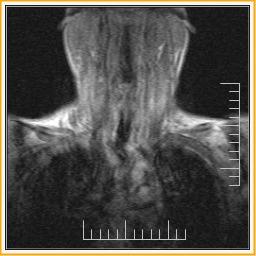

Cases